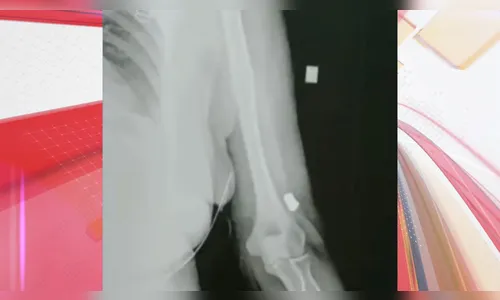

Autor Bala perdida foi encontrada no braço da vítima de 58 anos - Foto: Reprodução

Posteriormente, ao ser examinada na UPA, os profissionais de saúde identificaram a presença de uma bala alojada no braço da vítima.